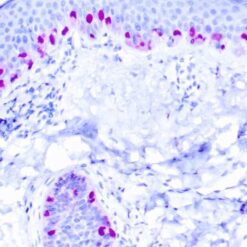

Synaptophysin (SYP02)

This antibody isspecific to a 38 kDa protein. Synaptophysin is an glycoprotein occurring in presynaptic vesicles of neurons in the brain, spinal cord, retina, vesicles of adrenal medulla and in neuromuscular junctions. This antibody reacts with neuroendocrine neoplasms of neural as well as epithelial types.

| Clone | SYP02 |

| Cellular Localization | Cytoplasmic |

| Positive Control Tissue | Pancreas |